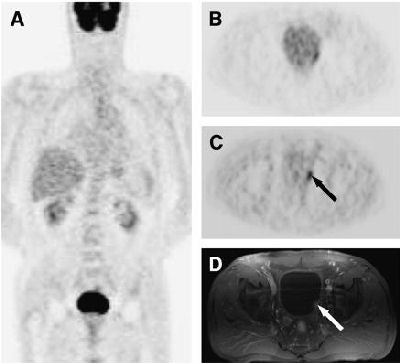

| A 69-year-old man with papillary bladder cancer. (A) Coronal prediuretic F-18 FDG-PET image shows complete masking of primary tumor by urinary activity. (B) Transaxial postdiuretic F-18 FDG-PET image after two voidings of urinary bladder shows equivocal finding. (C and D) Transaxial postdiuretic F-18 FDG-PET after three voidings (C) and correlative MRI (D) reveal T1 tumor in left lateral wall of bladder (arrows). Copyright © by the Society of Nuclear Medicine Inc. |

The protocol proved very effective for FDG-PET imaging of primary bladder cancer. The researchers reported clearly visualizing nine primary and two recurrent bladder tumors after discarding the residual F-18 FDG urinary activity.